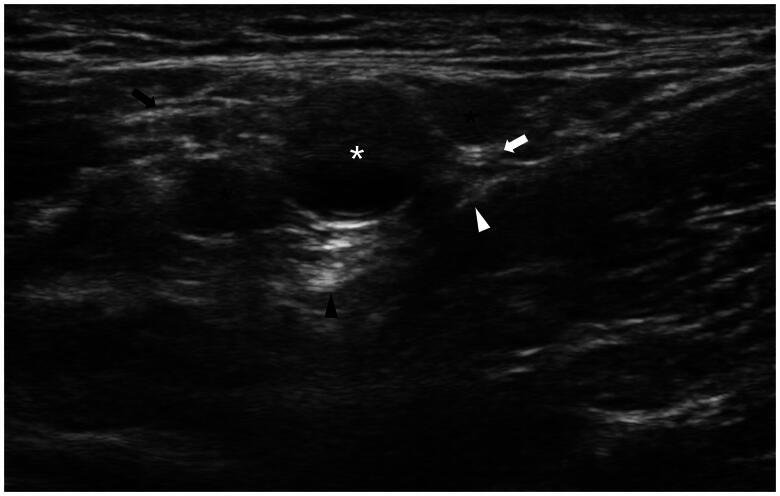

Objective: The study aimed to compare ultrasound-guided brachial plexus block (BPB) with local anesthesia (LA) on efficacy, safety and 12-month patency rate for percutaneous transluminal angioplasty (PTA) treatment of dysfunctional arteriovenous fistula (AVF).

Methods: Consecutive patients with dysfunctional AVF who underwent PTA from January 2021 to December 2022 were included. Overlap weighting was performed to adjust for significant differences between the two groups. The primary efficacy outcomes included visual analogue scale (VAS) score and 12-month target-lesion primary patency rate. The secondary efficacy outcomes included target-lesion primary-assisted patency rate, secondary patency rate, access-circuit thrombosis rate, access-circuit reintervention rate, and number of reinterventions within 12 months. Univariate analysis and multivariate analysis by log-binomial regression were used to identify the independent factors associated with intraoperative pain.

Results: 218 patients were included in the study: 82 patients underwent PTA under BPB and 136 patients underwent PTA under LA. After overlap weighting, the baseline, lesion characteristics and intraoperative details had no significant difference between the two groups. Patients under BPB had significantly lower VAS scores than those under LA (2.4 ± 1.4 vs 5.1 ± 1.9, p < 0.001). The 12-month target-lesion primary patency rate was significantly higher in the BPB group than that in the LA group (58.3% vs 40.0%, p = 0.037). The 12-month target-lesion primary-assisted patency rate and access-circuit secondary patency rate were significantly higher in the BPB group than those in the LA group (p = 0.023 and p = 0.028). The access-circuit thrombosis rate was significantly lower in the BPB group (10.0%) than that in the LA group (28.3%) (p = 0.011). BPB was the only independent factor associated with mild pain (p < 0.001, OR: 0.037, 95%CI: 0.011-0.119).

Conclusions: BPB could decrease the intraoperative pain and improve the 12-month primary patency rates compared with LA for patients underwent PTA treatment of dysfunctional AVF.